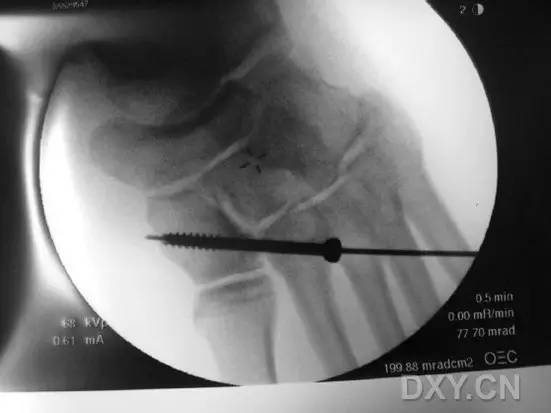

然而这种固定方式存在一大缺陷,那就是,一旦出现螺钉的断裂,将导致螺钉头端取出困难(图 2)。

图 2. 传统 Lisfranc 螺钉置入后,螺钉断裂,位于第 2 跖骨基底的螺钉尖端难以取出